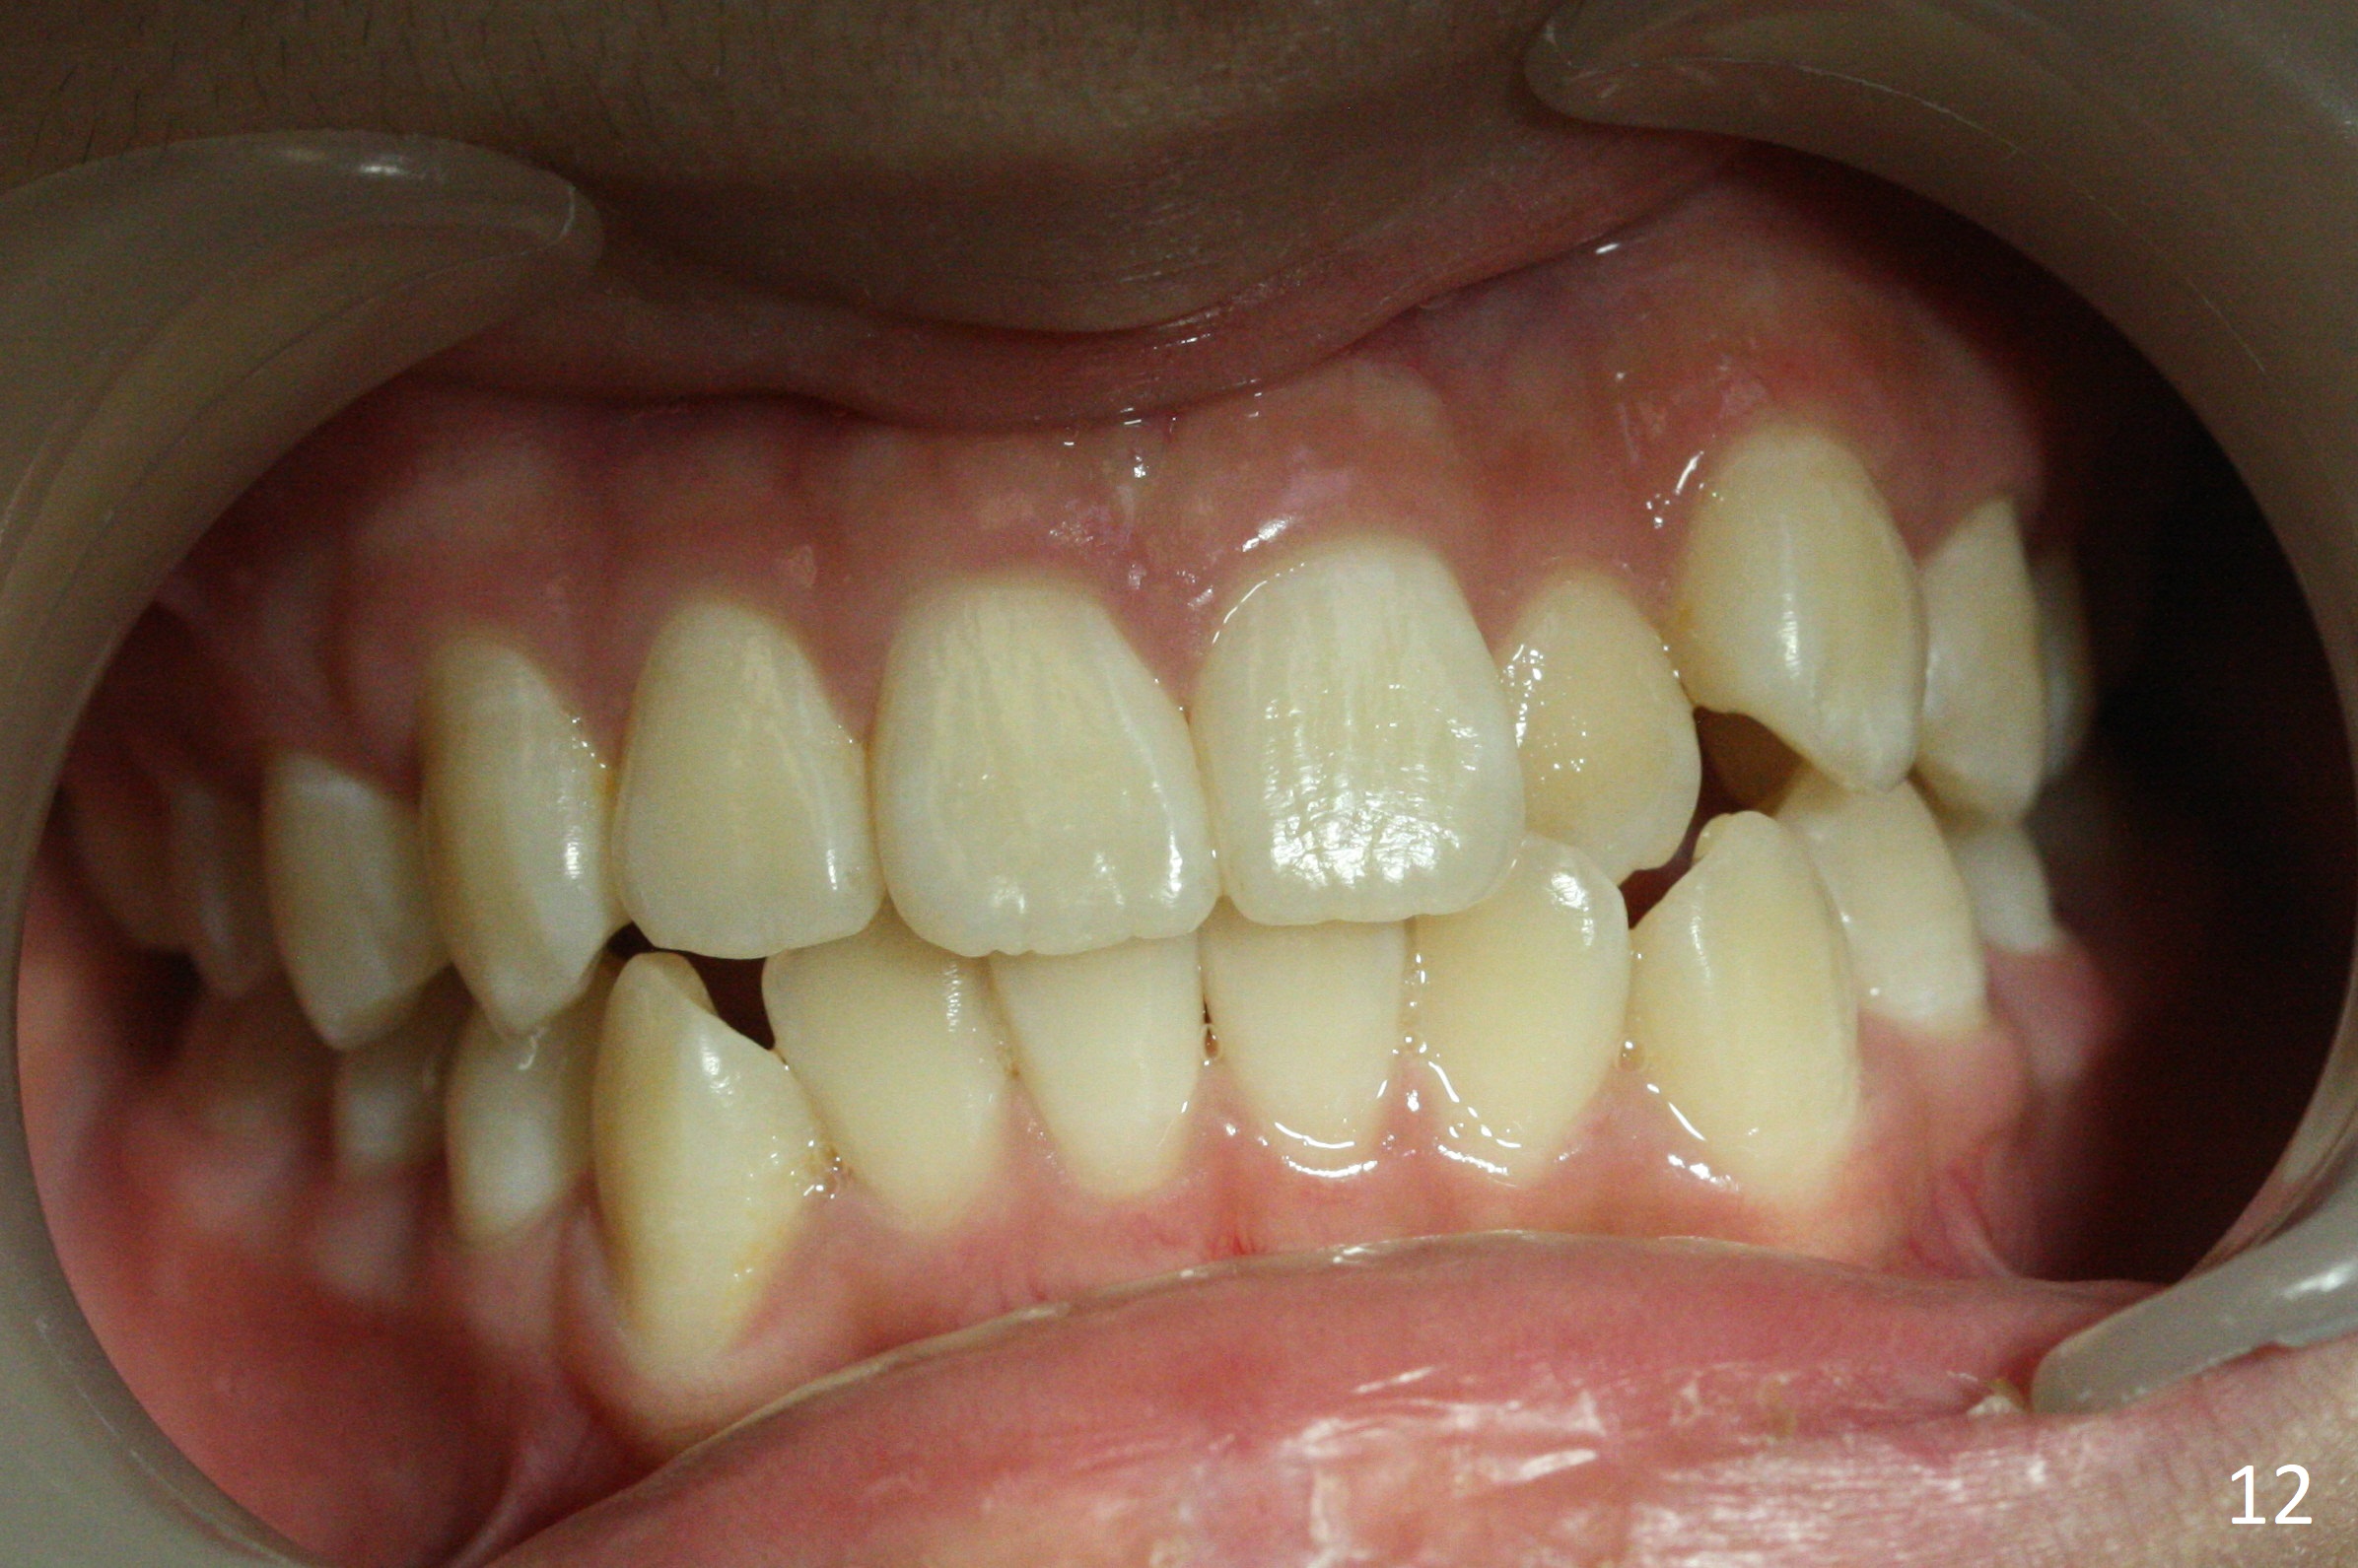

Shallow Overbite

A 12-year-old man has mild lip protrusion (Fig.1,6,7). Orthodontics will be conducted without extraction. Unlike his elder brother, the overbite is shallow. With anterior bracket differential (4-4-5 mm) and mild bimaxillary protrusion, open bite will be created? Or 4-4-4.5mm scheme should be adopted to avoid open bite?